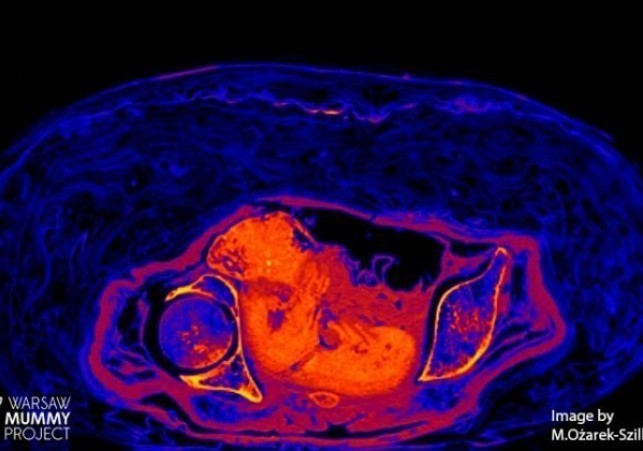

plod mumii

Płód w mumii egipskiej zachowany dzięki nietypowemu procesowi rozkładu

Płód znajdujący się w zmumifikowanej Egipcjance sprzed ponad dwóch tysięcy lat przetrwał do naszych czasów za sprawą bardzo nietypowego procesu rozkładu.… Czytaj więcej